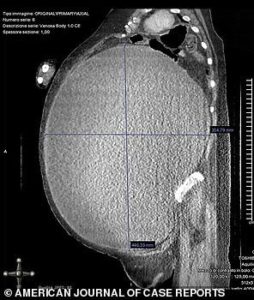

Bilim insanları ve doktorlar bu durum karşısında şoke olurken kadın aceleyle ameliyata alındı. 6.5 saat süren zorlu bir ameliyat süreci sonrasında yaklaşık 5 kilogramlık bir kist alındı.

Doktorlar vücutta birikmiş 37 litrelik suyu da boşaltmayı başardı. Kistin 40 santimetre uzunluğunda olduğu da belirtilirken, kadının yıllarca bu durumun farkına varmaması ve doktora gitmemesinin de süreci zorlaştıran faktörlerden olduğu anlaşıldı.